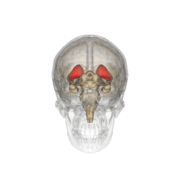

The caudate nuclei are located near the center of the brain, sitting astride the thalamus. There is a caudate nucleus within each hemisphere of the brain. Individually, they resemble a C-shape structure with a wider "head" (caput in Latin) at the front, tapering to a "body" (corpus) and a "tail" (cauda). Sometimes a part of the caudate nucleus is referred to as the "knee" (genu).[5]